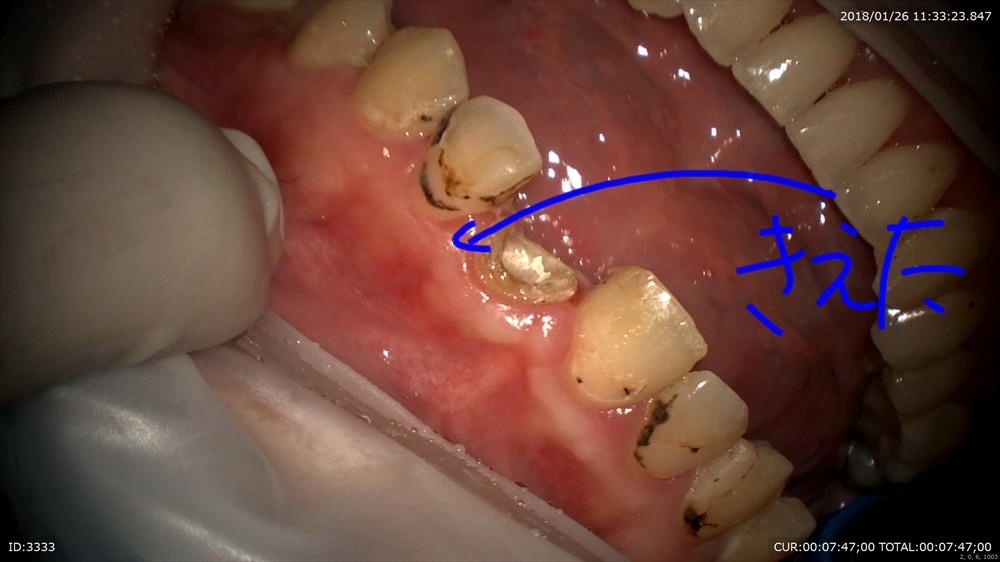

むし歯治療 穴があいていますね。

むし歯は大体中で広がります。 検知液で確認

綺麗にして型取り。次回で終わりです!